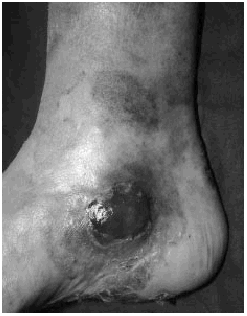

En seis de 50 pacientes con MF/SS (12%) se desarrolló transformación a LCG (tabla I). Todos ellos eran varones y la edad media fue de 61 años (intervalo: 49-77). La localización inicial del LCG fue en la piel en cuatro casos, en los que se manifestó de forma de tumores cutáneos de crecimiento rápido, excrecentes, infiltrados en base, de coloración violácea y superficie lisa o erosiva con escamocostra superficial (Figs. 1 y 2). Los dos casos restantes se presentaron con clínica extracutánea, uno en forma de adenopatías axilares y otro con un cuadro de dolor abdominal por invasión de la pared gástrica.

FIG. 2.--Tumor localizado en cara interna de tobillo, de tonalidad violácea y superficie erosiva.